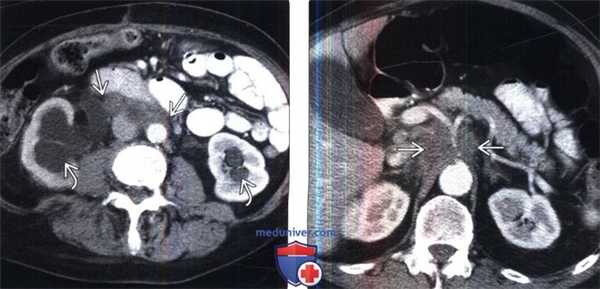

(Слева) КТ с контрастированием, аксиальная проекция: визуализирован двусторонний гидронефроз вследствие слившихся узловых метастазов забрюшинного пространства, ставших причиной мочеточниковой обструкции.

(Справа) КТ с контрастированием, аксиальная проекция: слившиеся узлы, окружающие чревный ствол, вследствие метастазирования рака пищевода. Рак дистального отдела пищевода часто метастазирует в верхние лимфатические узлы брюшной полости, печень или легкие.